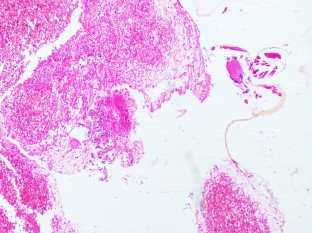

Enterobius vermicularis Infection of the Uterine Endometrium in an Infertile Female

Fig. 1

Fig. 2